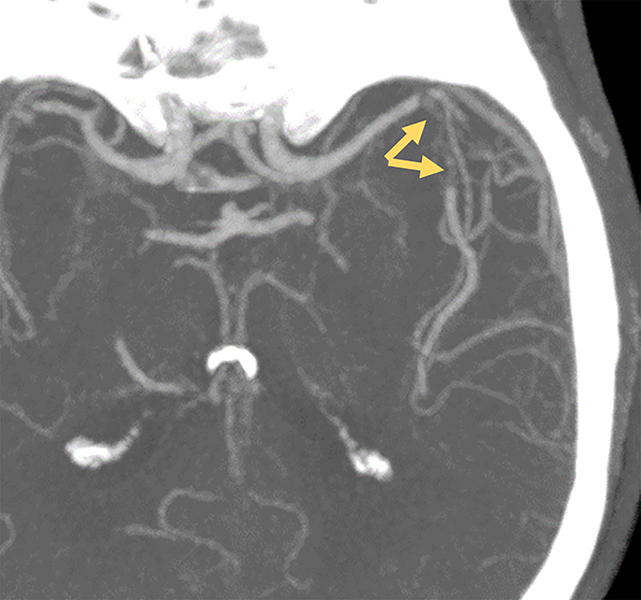

Teaching point: Spectral tomography offers valuable complementary diagnostic tools in the setting of cerebral fat macroembolism, a rare condition often presenting with nonspecific clinical symptoms.

Abstract Image